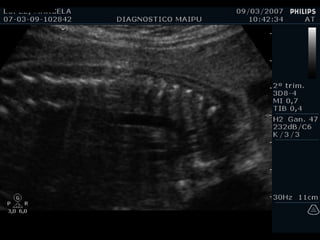

EXAMEN BASICO VENTRICULOS Tamaños Paredes Banda moderadora Tabique

Tamaño

Paredes

Banda moderadora

Tabique